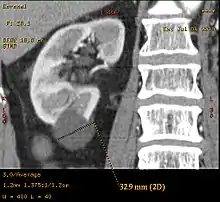

A Bosniak category IIF cyst. This one is 3 cm wide, with calcifications within its wall, seen as very radiodense (white in this presentation) areas in its margins. There is also a septation which is calcified. Yet, the cyst does not show enhancement (uptake of contrast).